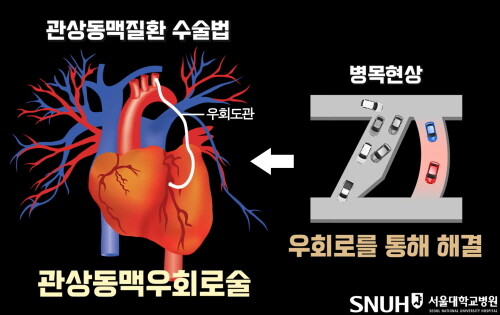

스타틴의 부작용으로는 근육통, 근력 약화, 간 기능 장애, 인지 기능 저하 등이 있으나 실제 임상 경험상 드물고 자가면역 혈관 질환(예: 타우, 동맥염 또는 가와사키병)과 관련이 있는 경우는 드물다. 신장이 제대로 기능하지 않는 경우 지연이나 검사가 필요하지 않을 수 있습니다. 흉통을 인지하고 적절한 치료를 받으면 관상동맥 질환의 위험을 줄일 수 있습니다. 광범위한 손상은 심각한 응급 상황과 만성 심부전으로 이어질 수 있으며, 이는 심장 기능 저하, 고콜레스테롤 및 스타틴 부작용으로 이어집니다. 협심증의 증상은 특히 흉골 전면 바로 아래의 가슴에 압박감, 조임 및 통증이 있습니다. YouTube를 서핑하고 일부를 본 다음 인터넷 검색에 어려움을 겪고 있습니다. 결국 어디 가서 정보를 수집하고 모두가 유명하다는 등 너무 많은 것을 추천합니까? 심장기능, 혈관질환, 석회화, 정도 등을 미리 예측할 수 있습니다. 관상동맥 석회화의 정도는 정상이고 일정 범위를 갖지만 경증, 중증, 중등도 및 고도의 관상동맥 석회화로 나눌 수 있습니다. 손상이 광범위하면 매우 위험한 응급 상황이 될 수 있으며 장기간 반복되면 심부전 및 심장 기능 저하로 이어질 수 있습니다. 수술적 합병증이 있을 수 있으나 심각한 기저질환이 없는 대부분의 환자에게 관상동맥우회술의 위험성은 약물복용 중 안전한 회복과 퇴원이다. 연구팀은 공복혈당과 당화혈색소에 따른 관상동맥석회화 위험도를 발표한 최인영 교수와 장유수 교수의 연구에서 관상동맥 석회화 위험이 1명에서도 증가했다. 당뇨병 이전 수준. 연민 이 상태에 있다면 건강한 생활 방식과 혈압, 혈당 및 콜레스테롤 수치 상승을 방지하는 방법을 실천하십시오. 유투브도 돌아다니고 영상도 보고 웹서핑도 하고. 결국, 모두가 마음으로 정보를 수집하고 유명하든 아니든 너무 많이 추천하고 싶다면 어디로 가야합니까?